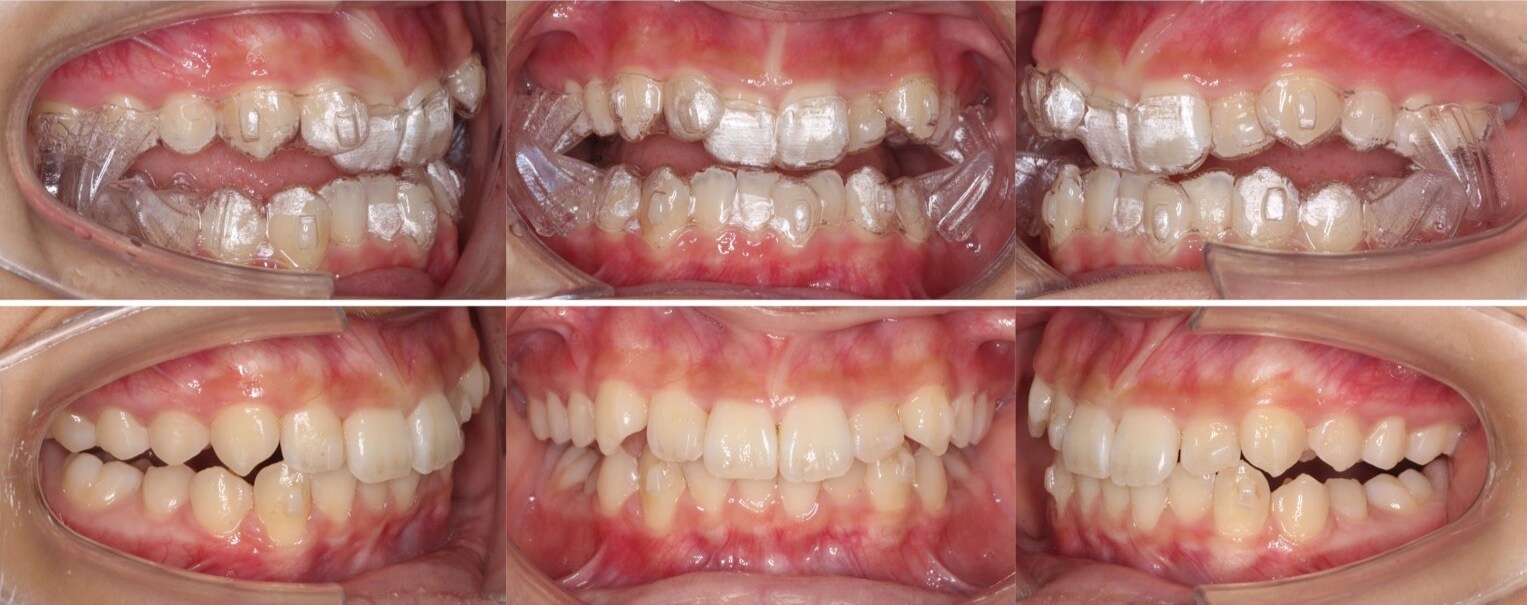

20代男性・マウスピース型装置・2本抜歯

抜歯を併用したマウスピース型矯正治療では、過蓋咬合の改善は難易度は高くなります。このケースは歯を動かすステージングの工夫と上手くバイトランプをうまく利用し改善しました。

<症例概要>

主訴:出っ歯

年齢・性別:20代男性

住まい:千葉県八千代市

症状:過蓋咬合・上顎前突・上下顎叢生

治療方針:バイトランプを使用した下顎前歯の段階的圧下

抜歯:上左右4番(計2本)

治療装置:マウスピース型矯正装置(アライナー装置)

治療期間:2年2か月

リテーナー:上下クリアタイプ+フィックスタイプ

治療費用:990,000(税込)

代表的副作用:痛み・治療後の後戻り・歯根吸収・歯髄壊死・歯肉退縮

▶︎その他の副作用

下の前歯と犬歯を交互に移動し、ゆっくりと確実に過蓋咬合を治します。

20代女性・ハーフリンガル・4本抜歯

過蓋咬合の抜歯症例は、マウスピース型矯正装置や上下の裏側装置での矯正治療は非常に難易度が高くなります。そこで上だけ裏側装置を使用したハーフリンガルにする事で、前歯のかみ合わせのコントロールを行いました。治療期間はかかりましたが、無事矯正治療を終える事ができました。

主訴:前歯のでこぼこ

年齢・性別:20代女性

住まい:千葉県船橋市

症状:過蓋咬合・叢生・上顎前突

治療方針:抜歯空隙の閉鎖(最大固定)

治療装置:ハーフリンガル矯正装置(上のみ裏側装置)

固定装置:歯科矯正用アンカースクリュー(口蓋側壁x2)

抜歯:上下左右4番(計4本)

治療期間:3年1か月

リテーナー:上下フィックスタイプ+プレートタイプ+クリアタイプ

治療費用:1,495,000(税込)